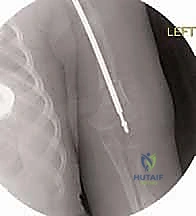

تُعد هذه العملية من أدق العمليات في جراحة عظام الأطفال، وتتطلب مهارة استثنائية كما هو الحال مع البروفيسور محمد هطيف. يتكون المسمار التلسكوبي (Fassier-Duval) من جزأين يتداخلان ببعضهما البعض (مثل التلسكوب). يتم تثبيت أحد الأطراف في أعلى العظم والطرف الآخر في أسفله. عندما ينمو العظم، ينزلق الجزء الداخلي من المسمار للخارج، مما يسمح للعظم بالنمو الطبيعي دون أن ينثني أو ينكسر.

بعد تقويم العظم وجعله مستقيماً كحبات المسبحة على خيط، يتم إدخال السلك الدليلي (Guide Wire). ثم يتم إدخال الجزء الخارجي (الأنثوي) من المسمار التلسكوبي وتثبيته في الجزء العلوي من العظم (Epiphysis).

بعد ذلك، يتم إدخال الجزء الداخلي (الذكري) من المسمار عبر الجزء السفلي من العظم وتثبيته في المشاشة السفلية. هذا التصميم العبقري يضمن حماية العظم بالكامل من الداخل.

المسمار العادي ذو طول ثابت، وعندما ينمو عظم الطفل، يصبح المسمار قصيراً ولا يحمي الأطراف الجديدة للعظم، مما يؤدي لكسرها. أما المسمار التلسكوبي فهو مصمم من قطعتين تتمددان مع نمو العظم (مثل هوائي الراديو القديم)، مما يوفر حماية دائمة للعظم طوال فترة النمو.